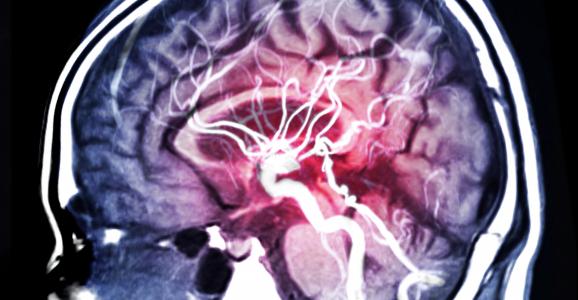

L'AVC ischémique, le plus courant, est causé par un caillot dans un vaisseau sanguin du cerveau. La perte soudaine du flux sanguin provoque la mort des cellules cérébrales, ce qui peut affecter de façon permanente la parole, la vision, l'équilibre et les mouvements. Cette recherche internationale d’une équipe de l’Université de Calgary (Canada) apporte l’espoir d’une meilleure récupération avec ces données prometteuses sur un nouveau médicament neuroprotecteur, le nérinetide. La molécule pourrait être très utile en combinaison avec la thérapie endovasculaire de reperfusion après un AVC ischémique. Cette efficacité du nérinetide, documentée dans le Lancet, promet enfin de pouvoir faire une grande différence pour les 15 millions de personnes qui souffrent d’AVC chaque année.

Vers un nouveau mode de prise en charge de l'AVC ? Les images du cerveau des patients montrent que la taille des dommages de l'AVC est considérablement réduite avec le nérinétide.